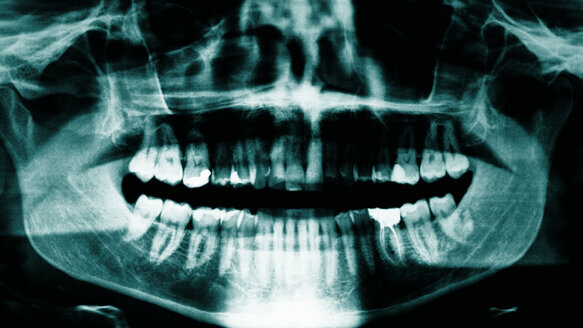

Bot past zich aan de eisen van mechanische belasting aan door zijn massa en structuur te veranderen. Zo bereikt het met een minimale hoeveelheid materiaal een maximale weerstand tegen mechanisch falen. Deze natuurlijke aanpassing vindt plaats tijdens de constante opbouw van botweefsel (botopbouw) en afbraak van bot (botresorptie) in een volwassen lichaam. Cellen genaamd osteoclasten breken bot af, osteoblasten bouwen bot op. Wanneer bot zich aanpast aan de mate van mechanische belasting (botremodellering) vindt botresorptie plaats door osteoclasten, terwijl osteoblasten nieuw bot aanmaken. De drukgevoelige osteocyten coördineren deze samenwerking. Wanneer osteocyten mechanisch belast worden, produceren ze signaalmoleculen zoals stikstofoxide dat de botvorming beïnvloedt.

De promovenda belastte botcellen mechanisch door een pulserende vloeistofstroom in kleine pulsjes over de botcellen te leiden. Naast mechanische belasting kunnen voedingsstoffen de stikstofoxidenproductie beïnvloeden. Voor een optimale botopbouw zijn eiwitten, vitamine C, vitamine D, vitamine A en mineralen als calcium, fosfor, magnesium en mangaan nodig.